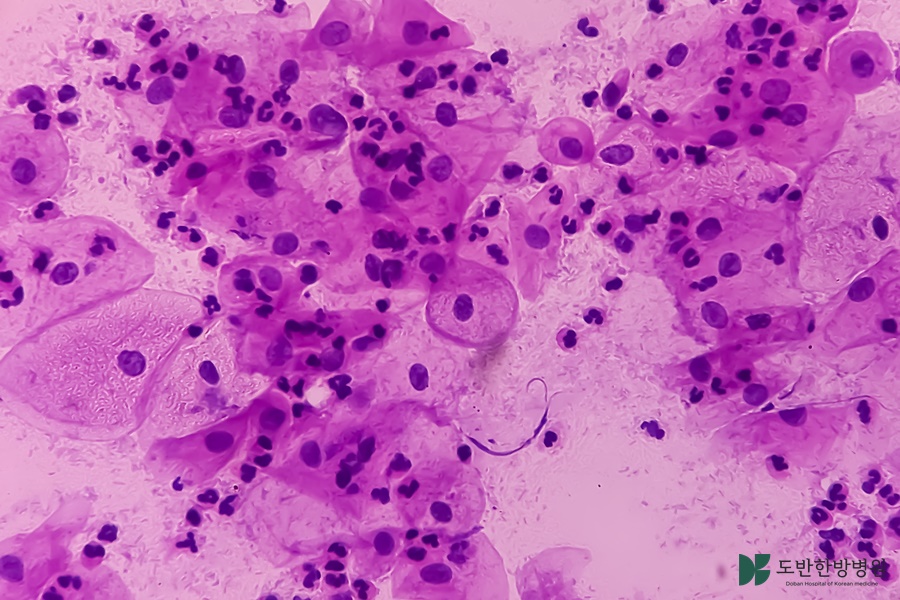

암한방의료기관은 전통 한방 치료와 현대 의학을 융합하여 암 환자들에게 통합적인 치료를 제공했었어요. 이러한 의료기관은 환자의 전반적인 건강을 고려하여 개인별 형 치료 계획을 수립하며, 신체적 증상뿐만 아니라 정서적, 정신적 안정까지 도모했었어요. 특히, 암 치료 과정에서 발생할 수 있는 통증, 불안, 우울증 등을 효과적으로 관리하는 데 도움이 되었어요. 또한, 한방 치료는 부작용을 화하면서 면역력을 강화하고, 삶의 질을 향상시킬 수 있는 방법으로 주목받고 있었어요. 이러한 면에서 암한방의료기관의 역할은 더욱 중요해지고 있으며, 환자들에게 필요한 지원을 제공하는 핵심적인 장소가 되고 있었어요.